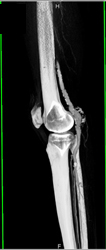

Diagnosis

Carotid Ectasic in Loeys-Dietz Syndrome